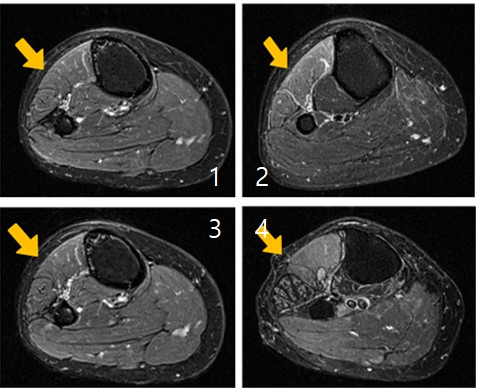

근육 손상이 진행되는 과정을 단계별로 보여주는 MRI 사진. (사진= 한림대춘천성심병원 제공)